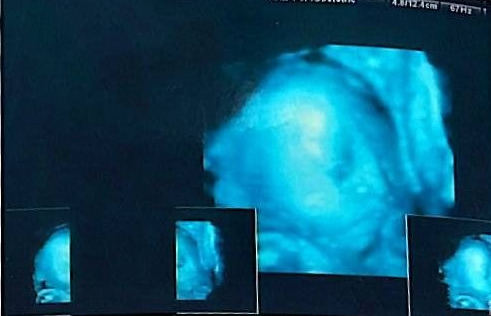

KakaoTalk_20250912_112244444_02.jpg 2003.1.13 입체 초음파 사진

00이가 얼굴을 잘 보여주지 않아서 엄마는 속이 상했단다.

겨우 옆얼굴을 찍었는데...

눈을 뜨지 않아서 정말 궁금하다.

코는 정말 아빠를 꼬옥 닮은 것 같은데...